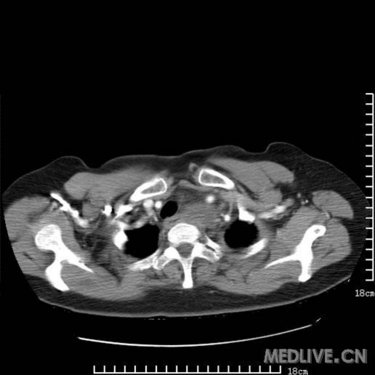

是胸腺瘤?畸胎瘤?高手支招_影像医学和核医学